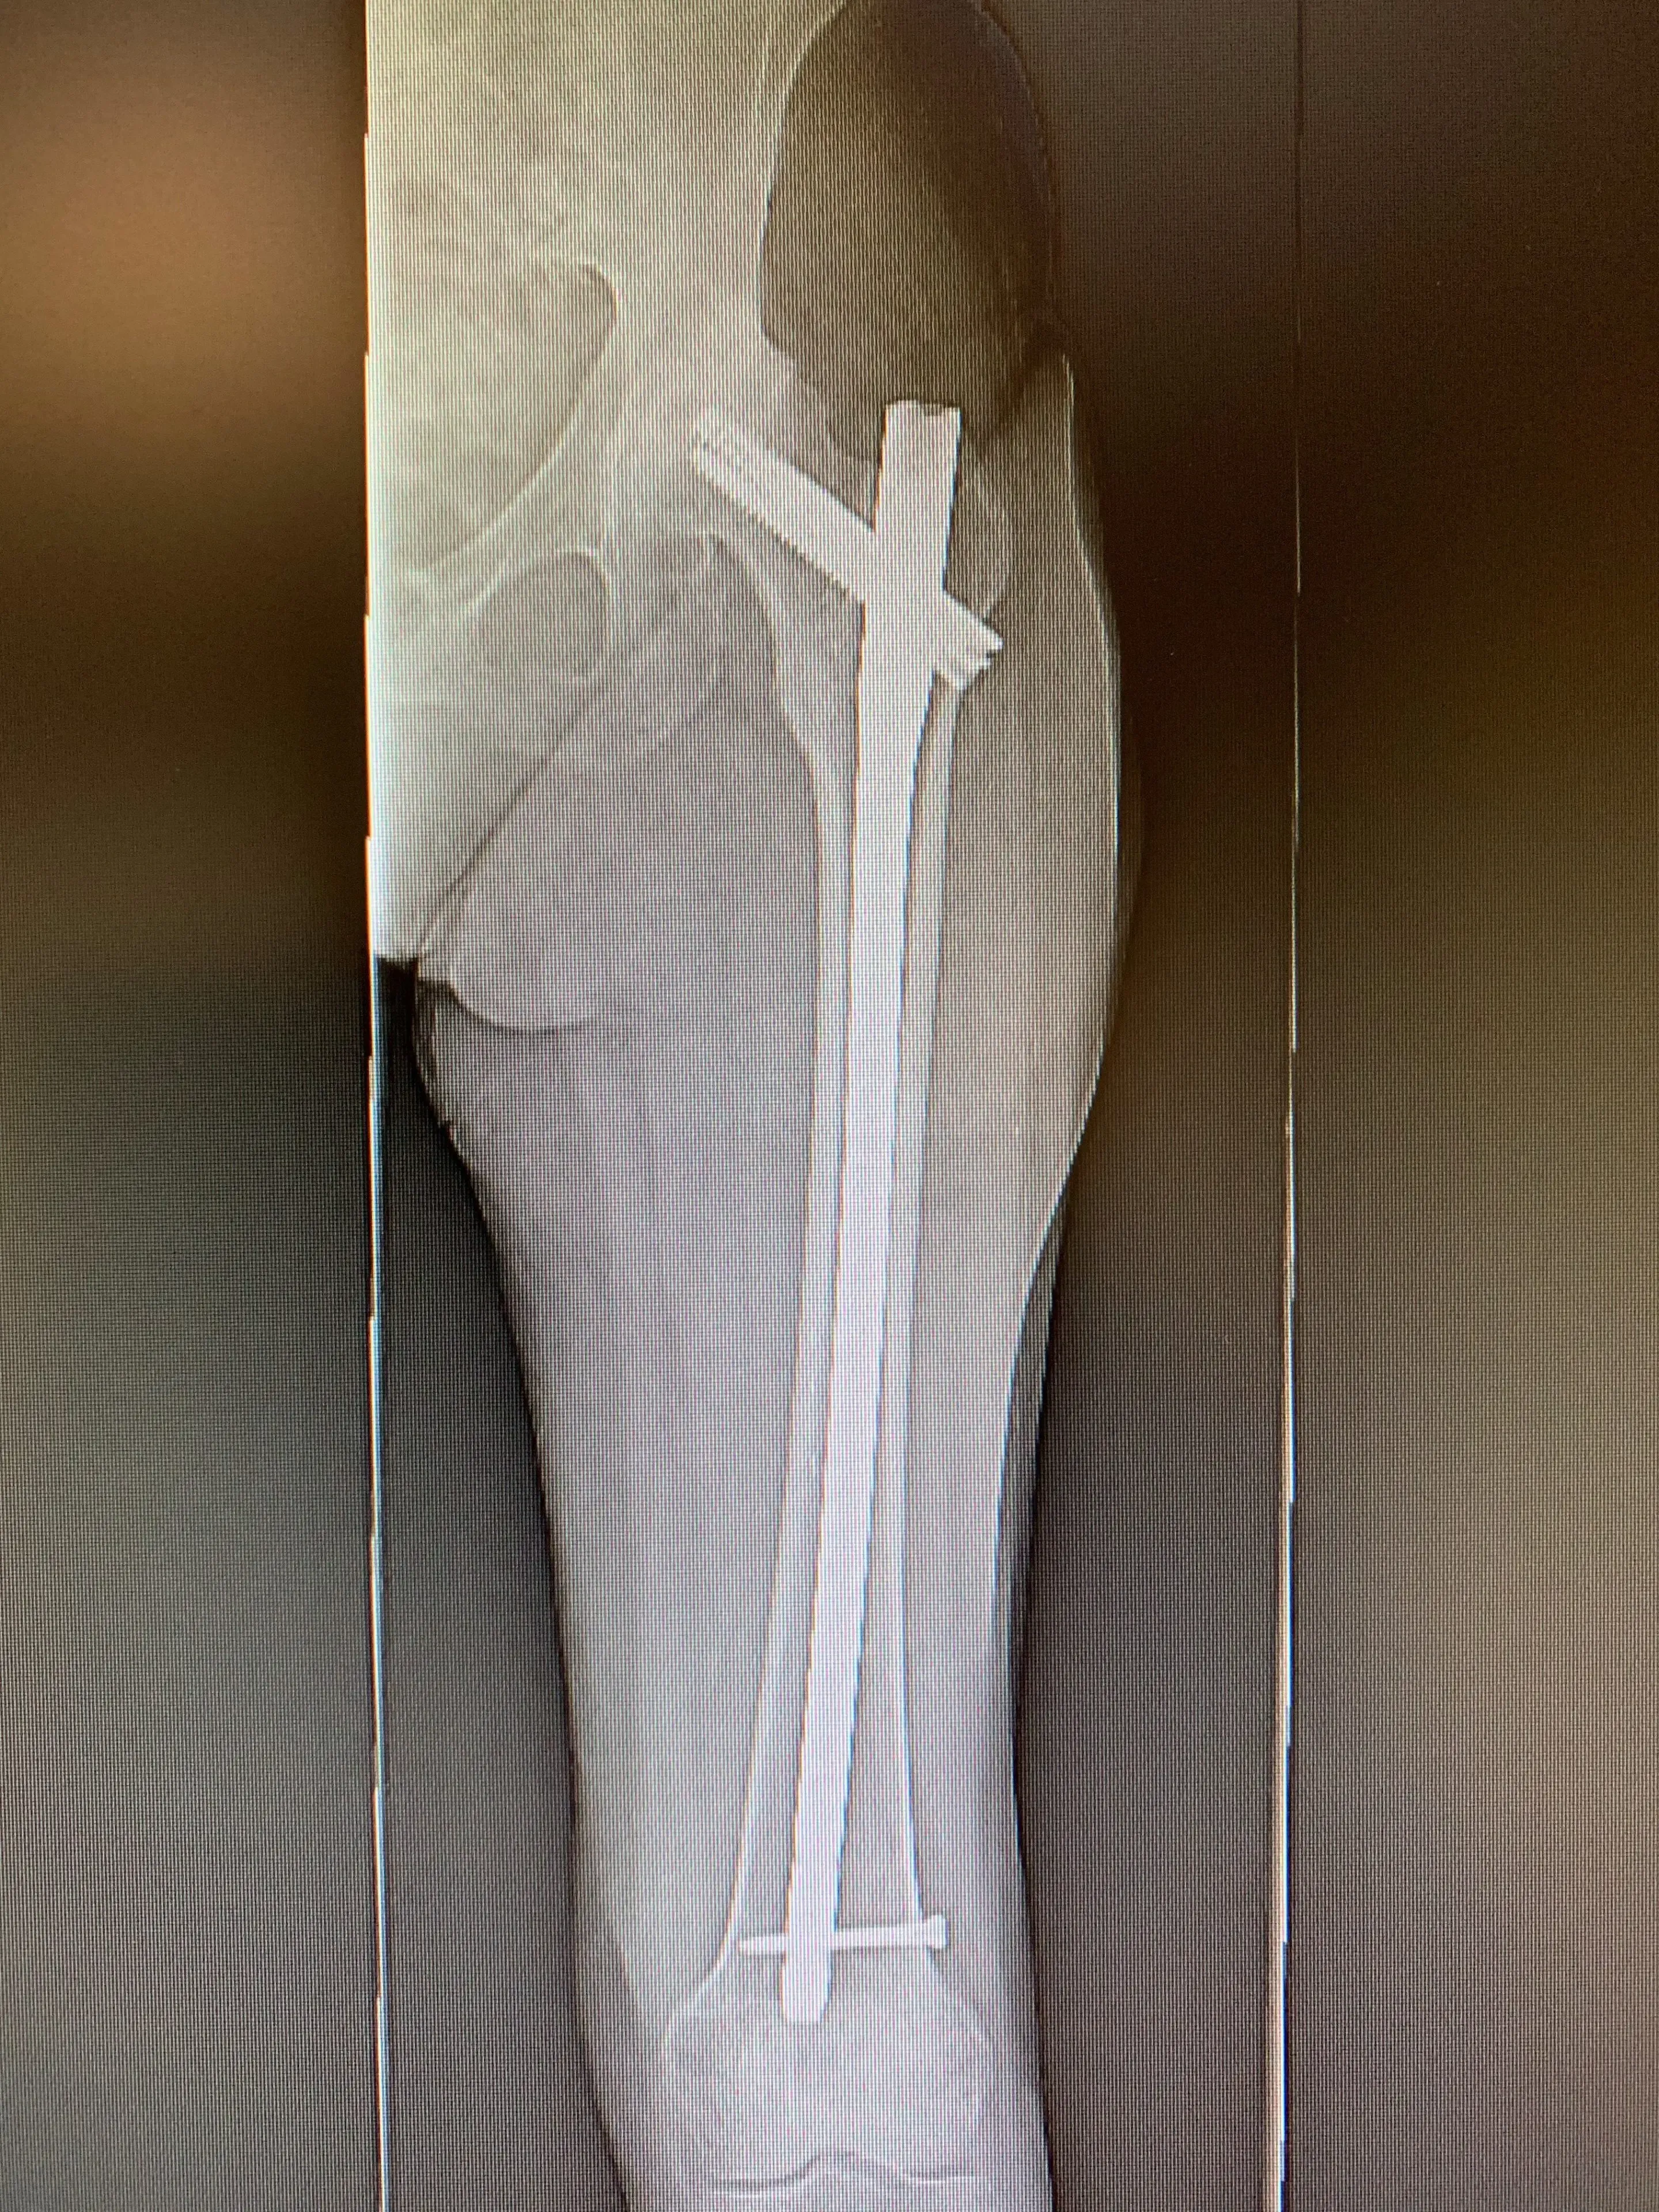

Her X-rays revealed her previous surgical hardware and a healed femur fracture with a small malunion in her femoral canal. Her hip was severely arthritic, with almost no joint space visible at all.

During her surgery, we first identified the insertion sites of the various components of her femur fracture hardware, and removed these carefully in the appropriate sequence. Once they were fully removed, we then began the hip replacement part of the procedure. Her acetabular component was placed without event, her femoral component proved more challenging to prepare for, given the new bone her body had formed in the area of the fracture. With careful removal of the bone blocking the femoral canal, we managed to implant a special femoral component that bypassed the site of the fracture, significantly reducing the risk of her femur fracturing again in the same area.

Pre-op